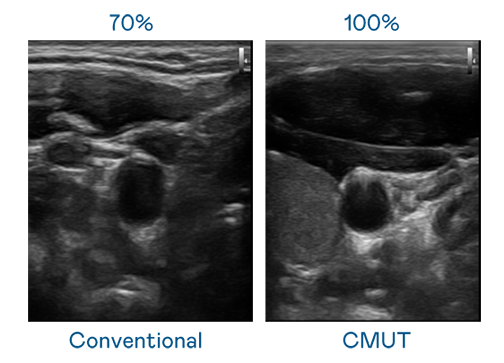

CMUT 技术是一种用电容式微机电元件来产生超音波讯号的技术。与传统 PZT 压电式技术相比,CMUT 频宽增加 30%,更宽频的超音波讯号让影像解析度大幅提升,是实现高影像品质医疗超音波扫描、促进精准医疗发展的关键技术。

大频宽带来超清晰影像

超音波影像的解析度高低,首先取决于探头能发出的讯号频宽。币赢 CMUT 可提供高清晰的超音波讯号,提供高频宽、高灵敏度、影像纹理细节更高的超音波影像,协助医护人员缩短影像判读时间及利用精准的医疗影像进行诊断。